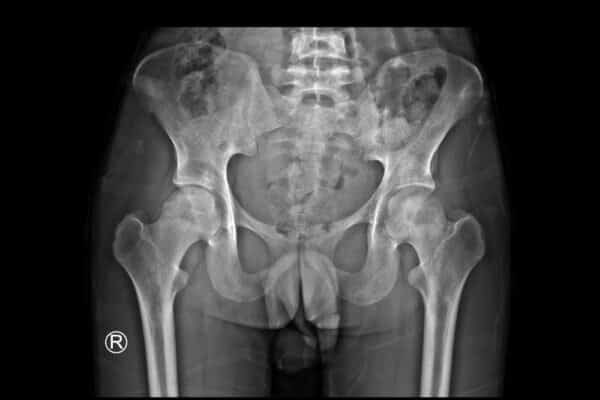

Information on Femoroacetabular Impingement Syndrome treatments

Marc Darrow, MD, JD. Many people contact us with problems of a confusion in their hip or low back diagnosis. They have confusion because they have had low back pain coupled with hip pain and after a long time trying to determine what was the cause of their pain, their doctors came back with a … Continue reading Information on Femoroacetabular Impingement Syndrome treatments